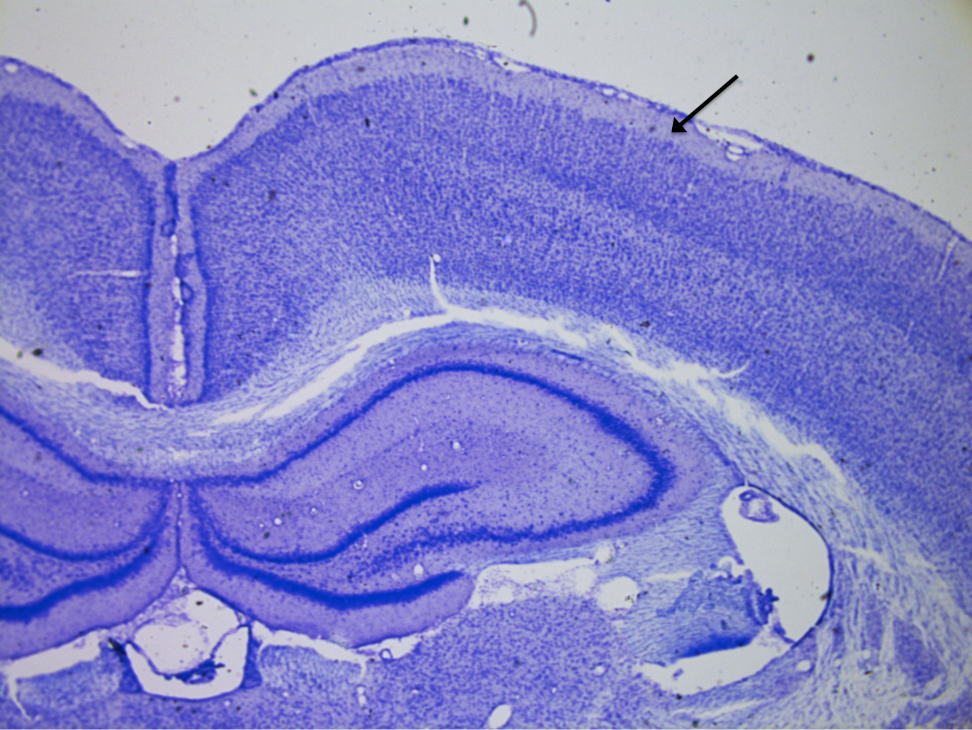

Cerebellum

knowt flashcard image